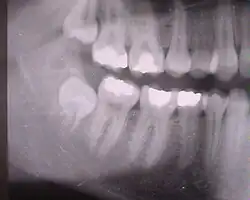

Eckzähne (rechter Bildrand), Prämolaren und Molaren (Bildmitte). Die Schneidezähne liegen rechts außerhalb des Bildausschnitts. Der untere Weisheitszahn ist noch nicht durchgebrochen und sein Wurzelwachstum ist noch nicht abgeschlossen.